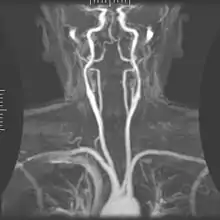

Magnetic resonance angiography (MRA) is a group of techniques based on magnetic resonance imaging (MRI) to image blood vessels. Magnetic resonance angiography is used to generate images of arteries (and less commonly veins) in order to evaluate them for stenosis (abnormal narrowing), occlusions, aneurysms (vessel wall dilatations, at risk of rupture) or other abnormalities. MRA is often used to evaluate the arteries of the neck and brain, the thoracic and abdominal aorta, the renal arteries, and the legs (the latter exam is often referred to as a "run-off").

MRA has been successful in studying many arteries in the body, including cerebral and other vessels in the head and neck, the aorta and its major branches in the thorax and abdomen, the renal arteries, and the arteries in the lower limbs. For the coronary arteries, however, MRA has been less successful than CT angiography or invasive catheter angiography. Most often, the underlying disease is atherosclerosis, but medical conditions like aneurysms or abnormal vascular anatomy can also be diagnosed.

MRA procedures for visualizing cranial circulation are no different from the positioning for a normal MRI brain. Immobilization within the head coil will be required. MRA is usually a part of the total MRI brain examination and adds approximately 10 minutes to the normal MRI protocol.